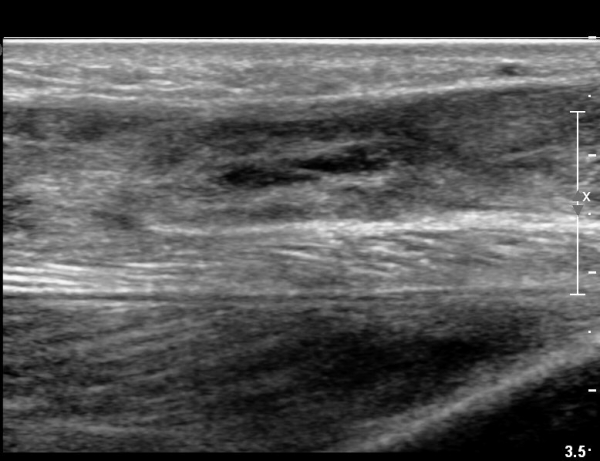

¾ÆÅ³·¹½º°Ç Ⱦ´Ü¸é°Ë»ç¿¡¼­  ¾ÆÅ³·¹½º°ÇÀÇ Àú¿¡ÄÚºÎÁ¾, ±¹¼ÒÀû ¿¬°á¼º ¼Ò½ÇÀÌ °üÂûµÊ(»çÁø 8).

2018³â  1¿ù 30ÀÏ ÃßÀû°Ë»ç

¾ÆÅ³·¹½º°Ç Àú¿¡ÄÚºÎÁ¾ÀÌ °¨¼ÒµÇ°í  ÆÄ¿­ºÎÀ§ Àú¿¡ÄÚ°¡ È£ÀüµÇ¾î

°ÇÀÇ ¼¶À¯¼º¾ç»ó(fibrillar pattern)ÀÌ È¸º¹µÇ°í ±¹¼ÒÀû ¿¬°á¼º ¼Ò½ÇÀÌ »ç¶óÁü(»çÁø 9, 10, 11, 12).